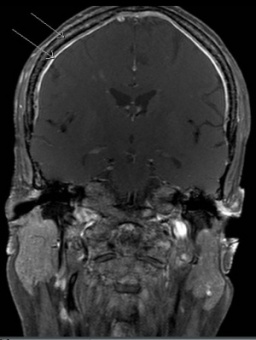

The abdomen and liver should be assessed by CT scan and/or MRI (Figure 4a). A chest CT should be performed if extension of abdominal disease or pulmonary metastasis is suspected. A MIBG scan should be performed to assess bone involvement. If the MIBG scan results are negative, a technetium 99 scan should be performed. Imaging with 123 I-MIBG is optimal for identifying soft tissue and bony metastases and is better than a PET/CT in prospective comparison.[50] If the primary tumor does not take up MIBG, additional imaging of isolated or equivocal positive lesions should be performed.[51] MRI of the spine should be performed to evaluate paraspinal tumors that may extend through neural foramina and compress the spinal cord (Figure 4b).

Figure 4a. Figure 4b.

56mm soft tissue mass in the R pelvis anterior to sacrum, to the Sagittal image of bony lytic lesions

right of the rectum. Soft tissue going into or out of the S4 neural compressing neural foramen.

foramen.